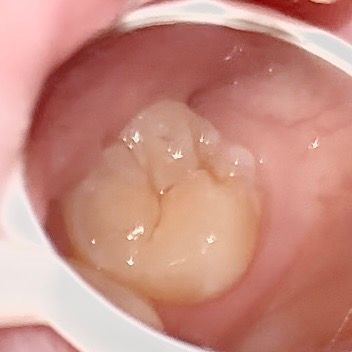

심각한 충치나 치수염 가능성이 있어보이나요??

심각한 충치나 치수염 가능성이 있어보이나요?? 치통인지 아님 생리전증후군인지.. 이쪽 부근에 은은한 통증? 불쾌감이 느껴져서요ㅜㅜ

• 3번 째 사진

치아 파절이 관찰되는데 파절 주위로 크랙이 의심됩니다 충치나 치수염이 아니더라도 크랙으로 통증이 심할 수 있습니다

이정도면 범랑질에 국한된 충치 입니다. 사진이 흐리지만 표면충치로 보이며 당분간 치료 안하고 그냥 지켜보다가 혹시 더 진행되면 충치치료 해도 될 것으로 보입니다.

사진 상으로는 단순 히 착색이 된 정도로 보이며 치수염이나 심한 충치가 의심되진 않습니다.

사진상으로 심각한 충치같이 보이거나 그렇진 않습니다. 간단한 충치치료를하면될것같습니다.